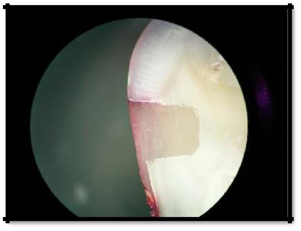

2. Penetration less than one half of the length of occlusal/gingival wall (Figure 5)

Figure 5 Penetration less than one half of the length of occlusal/gingival wall (Score 1).